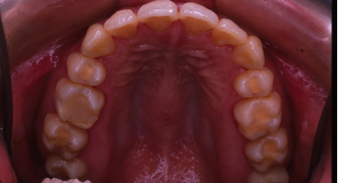

子供の開咬(かいこう)非抜歯

9歳/女の子

悩み:前歯の上下のすき間が気になる

拇指吸引癖(指しゃぶり)、舌突出癖(舌が前に出ている)、吸唇癖(唇を吸う)、咬唇癖(唇を噛む)により上下の歯の間に隙間(空隙)ができている

治療期間:約2年(成長期を追いながらの治療のため経過観察が必要)

治療前

前歯が噛めてないことでご両親が心配になり来院されました。

この開咬は指しゃぶりと舌が前に出る事によって、上下の間に隙間が出来ているので、クリブプレートという矯正装置を入れ、経過観察を行うことで自然治癒で直る治療を選択しました。経過観察のチェックのみで前歯部の開咬の治療が終了した症例です。